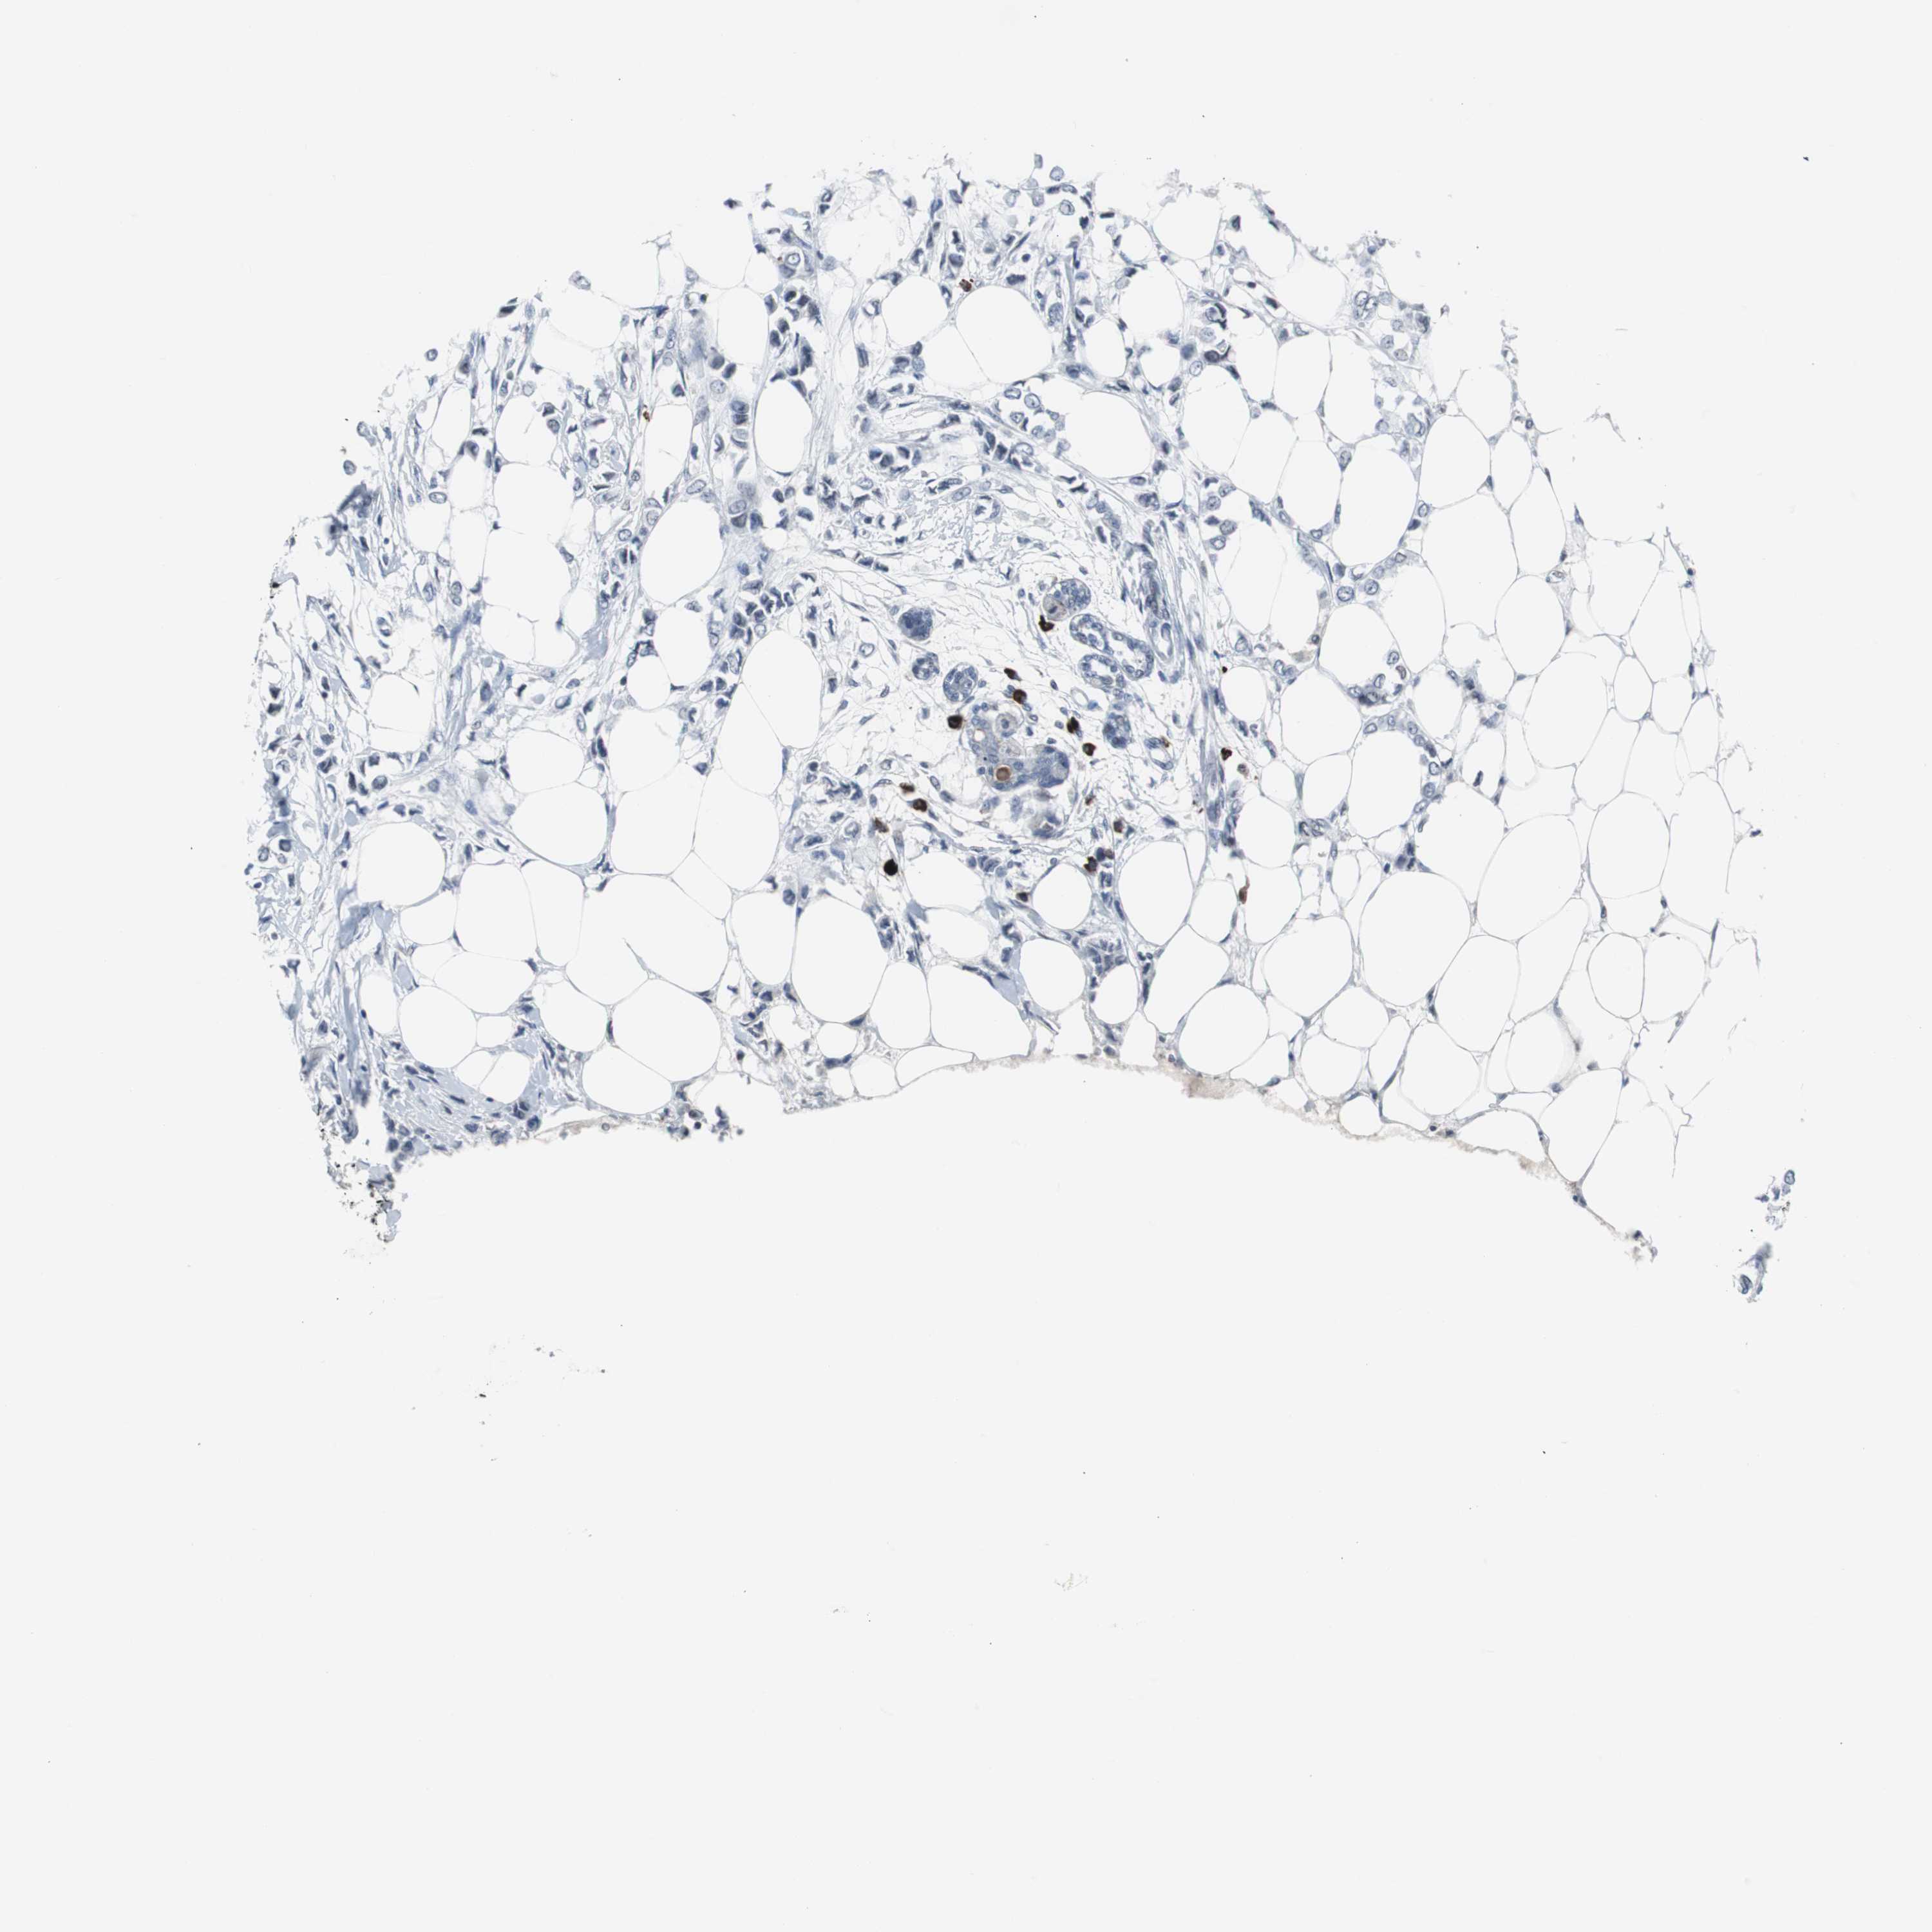

CANCER BREAST CANCER Show tissue menu

BRCA TCGA BRCA VALIDATION PROTEIN EXPRESSION

Breast cancer

Human cancer

Breast invasive carcinoma

DOK1 is not prognostic in Breast Invasive Carcinoma (TCGA)